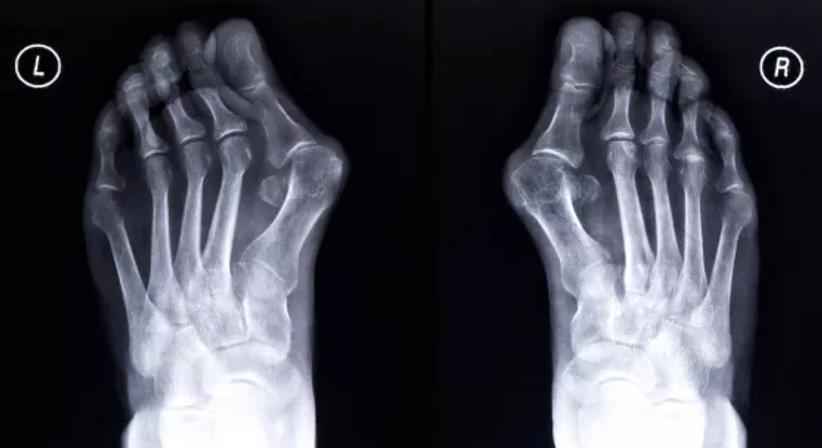

Der Hallux valgus ist die häufigste Fehlstellung des Fußes. Es handelt sich um eine Fehlstellung des Großzehengrundgelenks, bei welcher die Großzehe von ihrer normalen Ausrichtung nach außen abweicht und andere Zehen verdrängt. Typisch für einen Hallux valgus ist, dass das oft geschwollene Mittelfußköpfchen im Bereich vom Großzehengrundgelenk hervortritt und schmerzhaft gegen den Schuh drückt.

Anfangs ist ein Hallux valgus häufig nur ein kosmetisches Problem. Im weiteren Verlauf kann es dann zu einer Vielzahl an Beschwerden und Problemen kommen (Rötungen, Schwellungen, vergrößerter Ballen, Schmerzen, zunehmende Abweichung der Großzehe zur Seite, Verdrängung und Fehlstellungen benachbarter Zehen, Abnutzungen und mit Schmerzen einhergehende Versteifung des Großzehengrundgelenks, Überlastung kleinerer Zehen, veränderte Abrollbewegung des Fußes und Veränderungen im Gangbild u. a.). Das genaue Beschwerdebild kann individuell sehr verschieden sein.